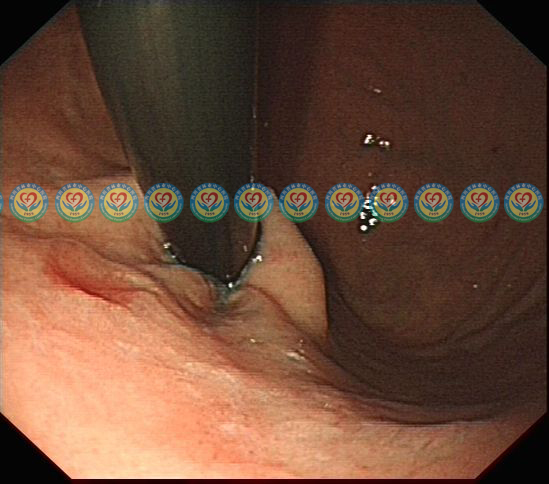

第一次胃镜检查,反转观察,贲门口下方(图片9点位置)见一发红浅凹陷病变、周围粘膜微隆起。活检提示:低级别上皮内瘤变